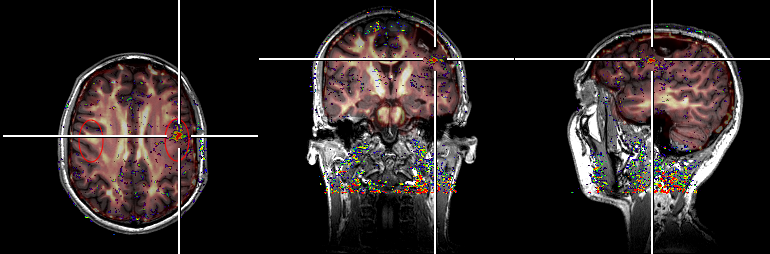

Simultaneous MR/PET images of an anthropomorphic head phantom. The three columns show different slices of the same phantom. Top row: PET images only. Bottom row: MR images only. Middle row: Overlay of MR and PET images. | Copyrights: Forschungszentrum Jülich

This combination of high resolution and sensitivity results in detailed images and precise data that provide valuable insights into the brain. By simultaneously capturing MRI and PET data under the same conditions, the BrainPET 7T insert sets new standards in PET/MRI imaging by eliminating the need for multiple examinations, which can be tedious and exhausting for patients. This technology will give researchers unprecedented access to the detailed workings of the brain in both health and disease, potentially improving the diagnosis and treatment of numerous neurological disorders and taking basic research to a new level.